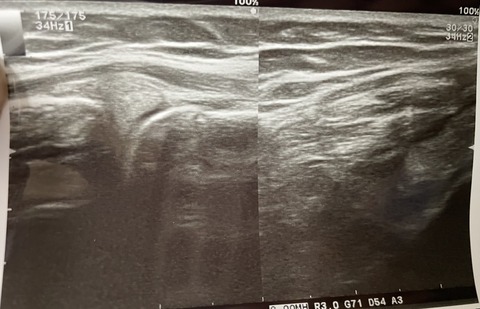

最近の最新型の超音波エコーは、

かなりの、有効性があります

さすがにMRIには勝てませんが、

筋損傷や靭帯損傷など、触診しながら

動的に画像が見えるため

MRIより優れているところもあります

5016668B-0D68-46F1-90CE-69F9E41BCE40

プロサッカー選手

MRI取らずに、エコーで、確定診断でき

1度の損傷と診断、トレーナーと連携して

2週間で復帰できました